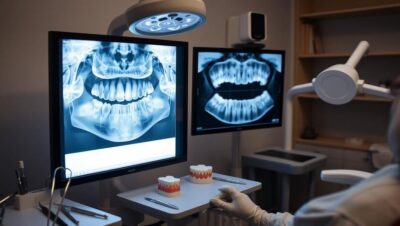

Panoramic Radiography for Overall Assessment of the Jaw and Teeth

Panoramic radiography is a common and essential method for evaluating the overall condition of the jaw and teeth in orthodontics. This radiography provides a wide image of all teeth, jaws, and related bone structures, helping dentists identify hidden issues like impacted teeth, cysts, and tumors. This type of radiography is also useful in assessing tooth growth stages and determining the appropriate timing for starting orthodontic treatment.